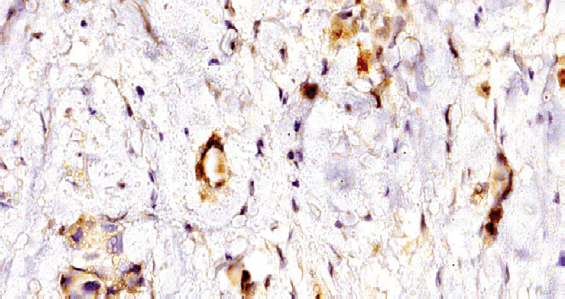

Results. In the group of triple negative breast cancer, 4 cases were detected expressing a cow leukosis virus antigen. Expression was represented by grains and clumps in the cytoplasm and on the surface of the tumor cell membrane, the wall of microvessels. Also in these cases, increased expression of VEGF was detected.

Conclusion. The results indicate that expression of the BLV antigen was observed only in cases of poorly differentiated triple negative breast cancer. It is also noteworthy that the same type of BRCA1 gene mutation (5382insC) and increased expression of vascular endothelial growth factor were detected in these tumors. The authors first used the immunohistochemical method for detecting the antigen of the BLV virus, which made it possible to reliably confirm its presence in breast tumors with similar molecular genetic and immunohistochemical profiles.